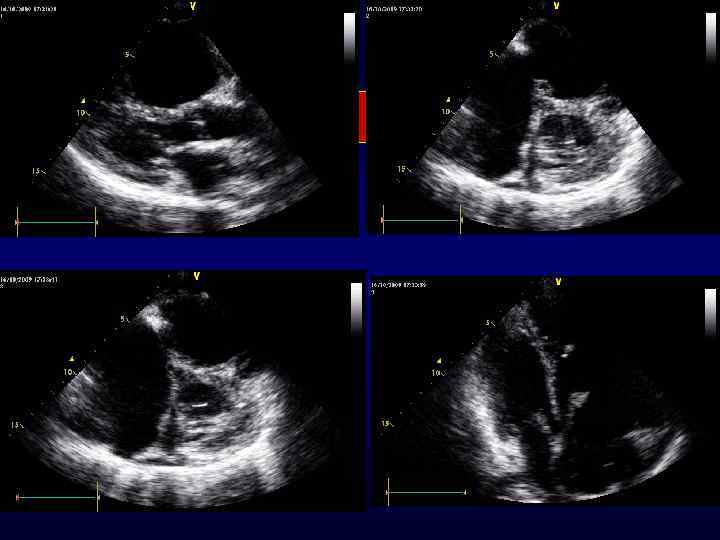

Вегетации

Большая мобильная вегетация на митральном клапане Диастола: вегетация в левом желудочке Систола: вегетация пролабирует в ЛП